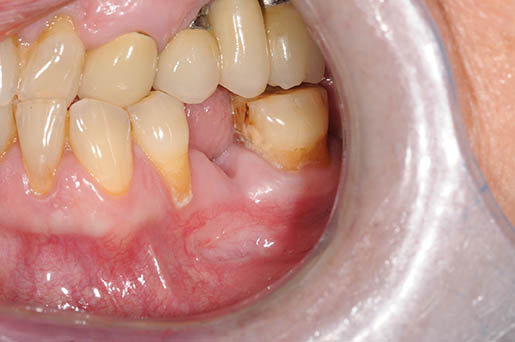

Osteonecrosi del mascellare superiore di destra

MRONJ e Definizione

“L’osteonecrosi delle ossa mascellari associata a farmaci (MRONJ) è un evento avverso farmaco-correlato, caratterizzato dalla progressiva distruzione e necrosi dell’osso mandibolare e/o mascellare di soggetti esposti al trattamento con farmaci per cui sia accertato un aumentato rischio di malattia, in assenza di un pregresso trattamento radiante”.

Questa definizione si basa su questi 3 parametri:

- trattamento in corso o precedente con agenti antiriassorbitivi o antiangiogenici

- osso mascellare esposto o osso che può essere sondato attraverso una fistola intraorale o extraorale nella regione maxillo-facciale che ha per- resistito per più di 8 settimane

- nessuna storia di radioterapia o metastasi delle ossa mascellari [11]

Segno clinico maggiore:

- Esposizione osso necrotico (Cavo orale)